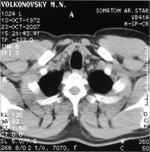

Я в разрезе

Октябрь 2007 года.